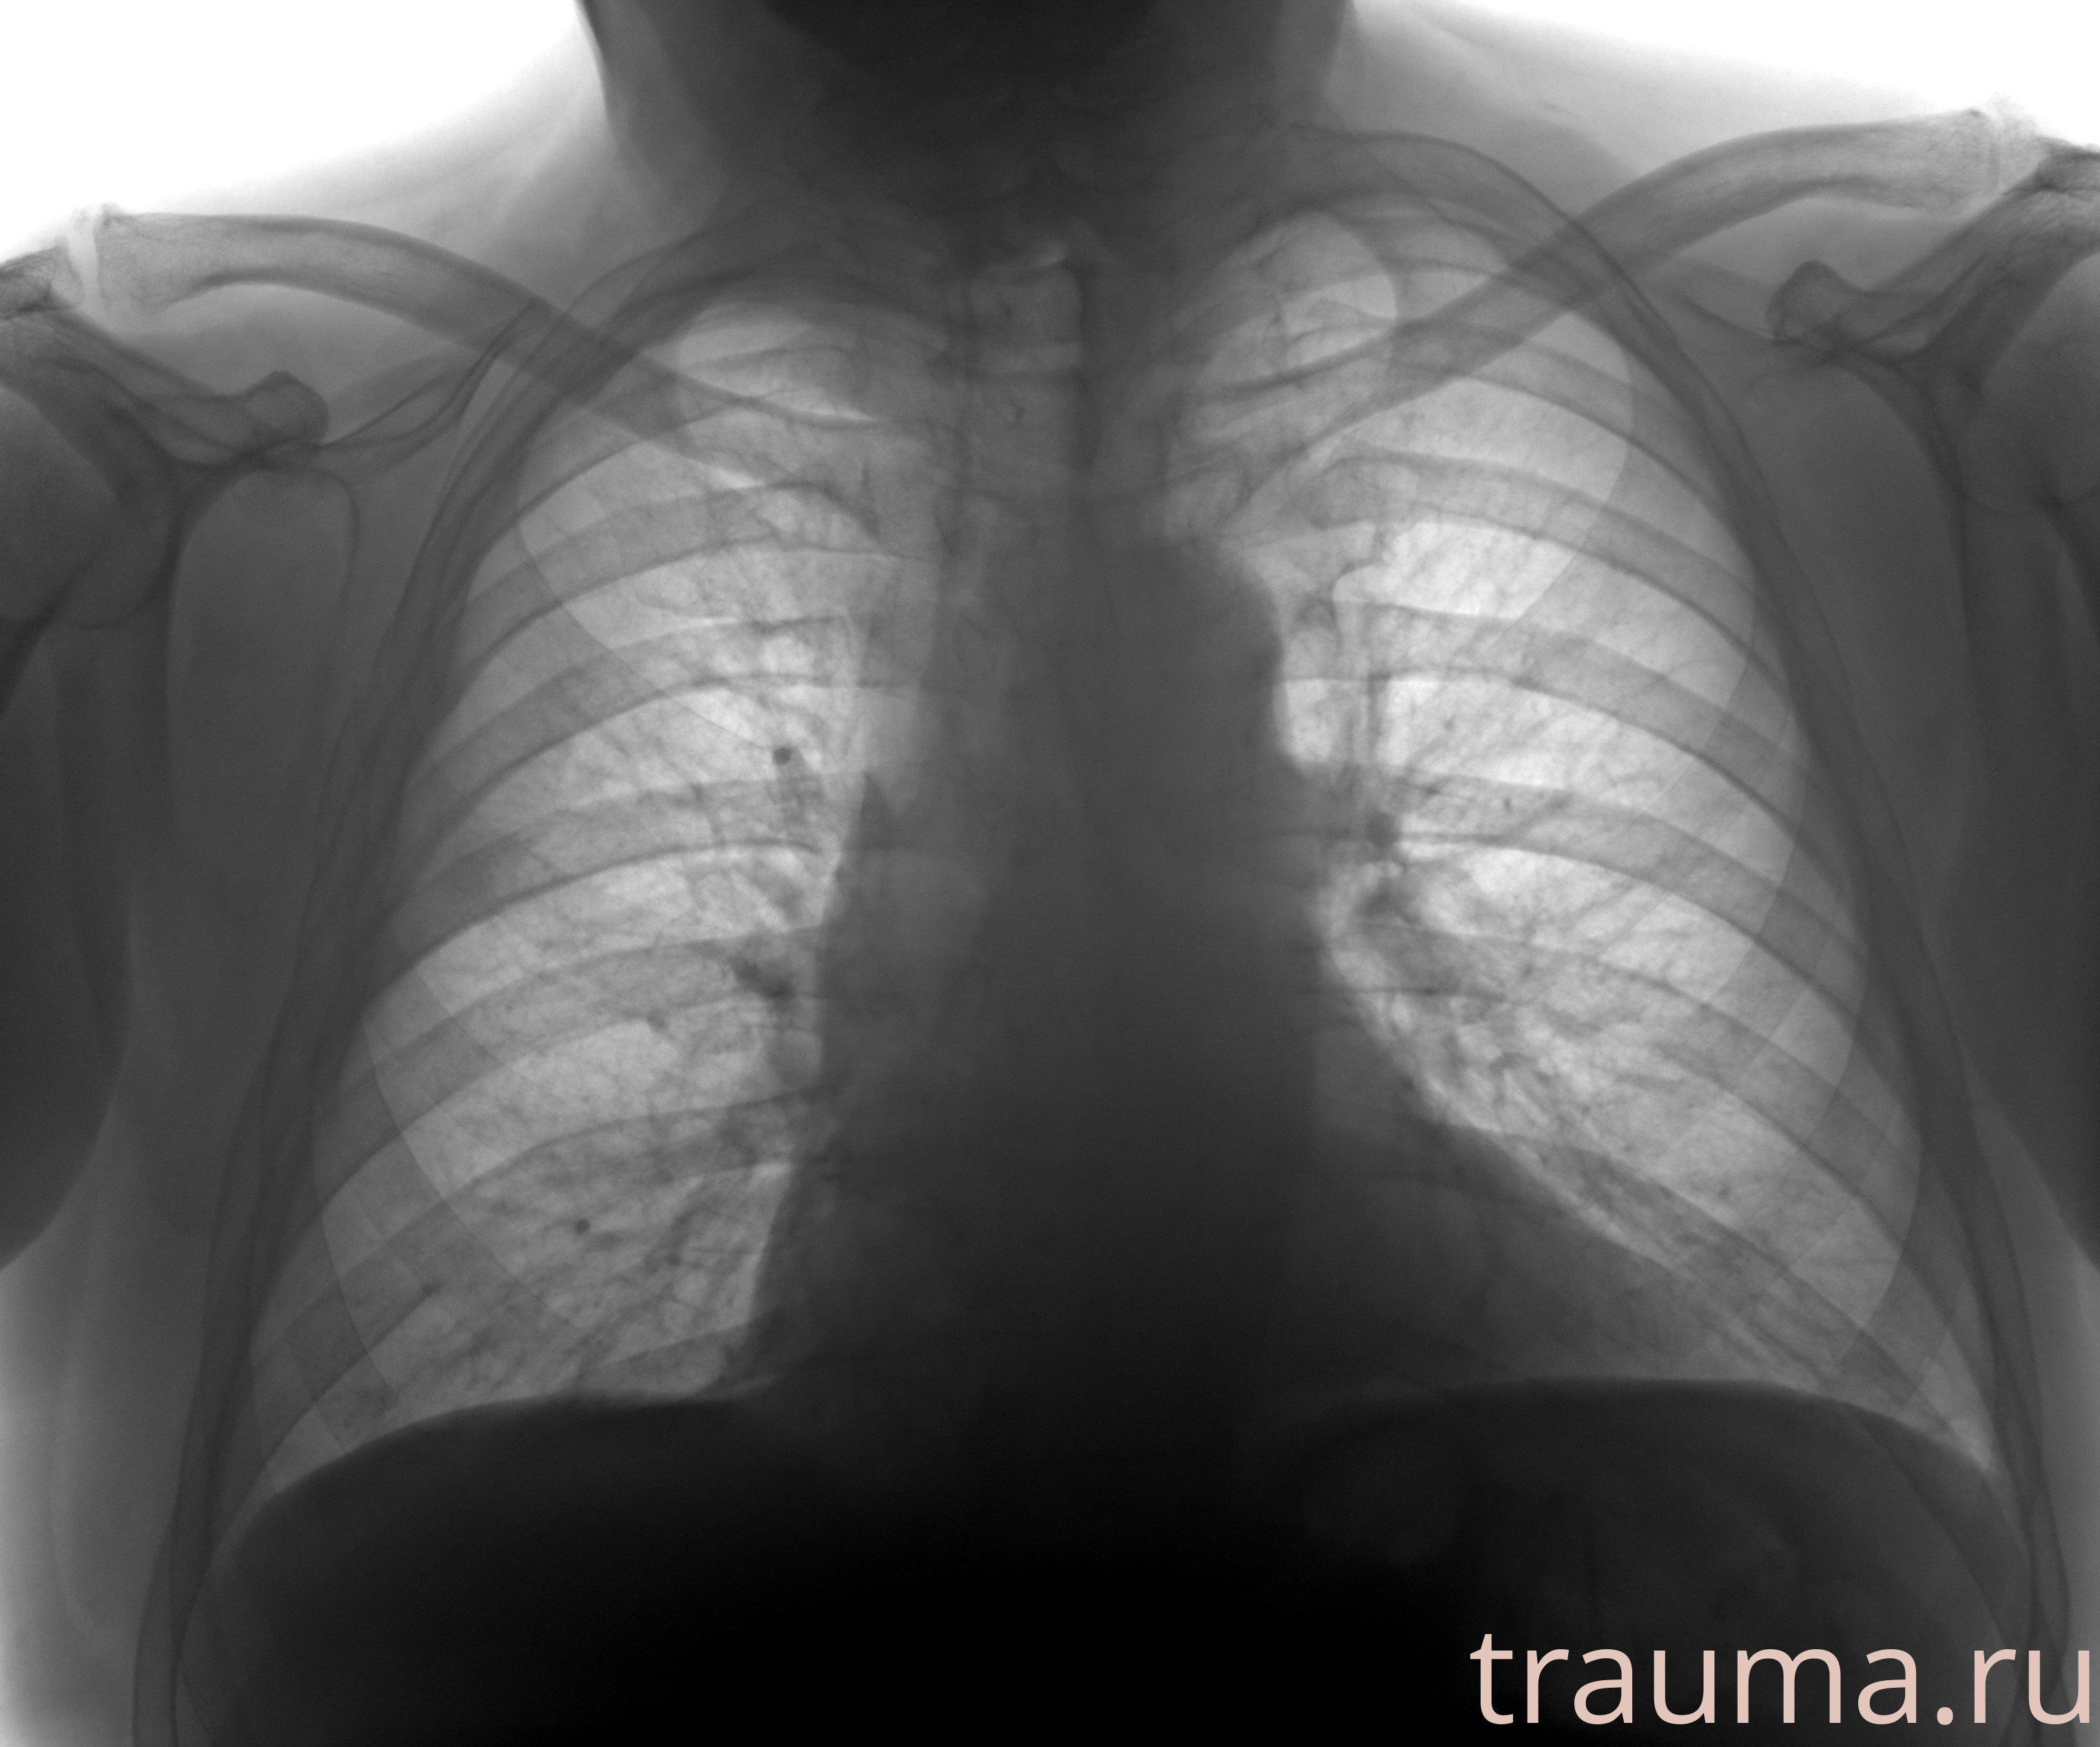

Рентгенограммы

Рентген на дому: по вашему адресу приезжает врач-рентгенолог, травматолог-ортопед с мобильным рентгеновским аппаратом, проводит диагностику травмы или заболевания, делает необходимые рентгенограммы, дает рекомендации по дальнейшему лечению. Получить качественные снимки в домашних условиях возможно благодаря уникальной методике, разработанной МосРентген Центром для института  Склифосовского